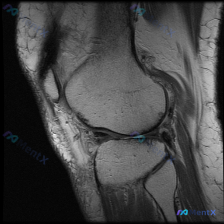

核心问题:患者主诉提示膝关节存在软骨异常,仅提供单张膝关节MRI-T1序列矢状位影像,已完成影像读片分析。

- 骨性结构:股骨远端、胫骨近端、髌骨骨皮质完整,无骨折,骨髓信号均匀,无明显异常低信号病灶

- 关节软骨:股骨髁、胫骨平台关节软骨厚度、连续性尚可,未见局灶性缺损或软骨下骨板暴露

- 半月板与韧带:半月板形态完整,内部信号均匀,无明确贯穿关节面的高信号;前后交叉韧带、髌腱连续性好,信号正常,无撕裂表现

- 其他结构:关节腔内无明显积液,滑膜无增厚,髌下脂肪垫信号正常,腘窝无异常占位

影像总结:这张T1矢状位MRI未见明确的膝关节结构性损伤或软骨异常改变。